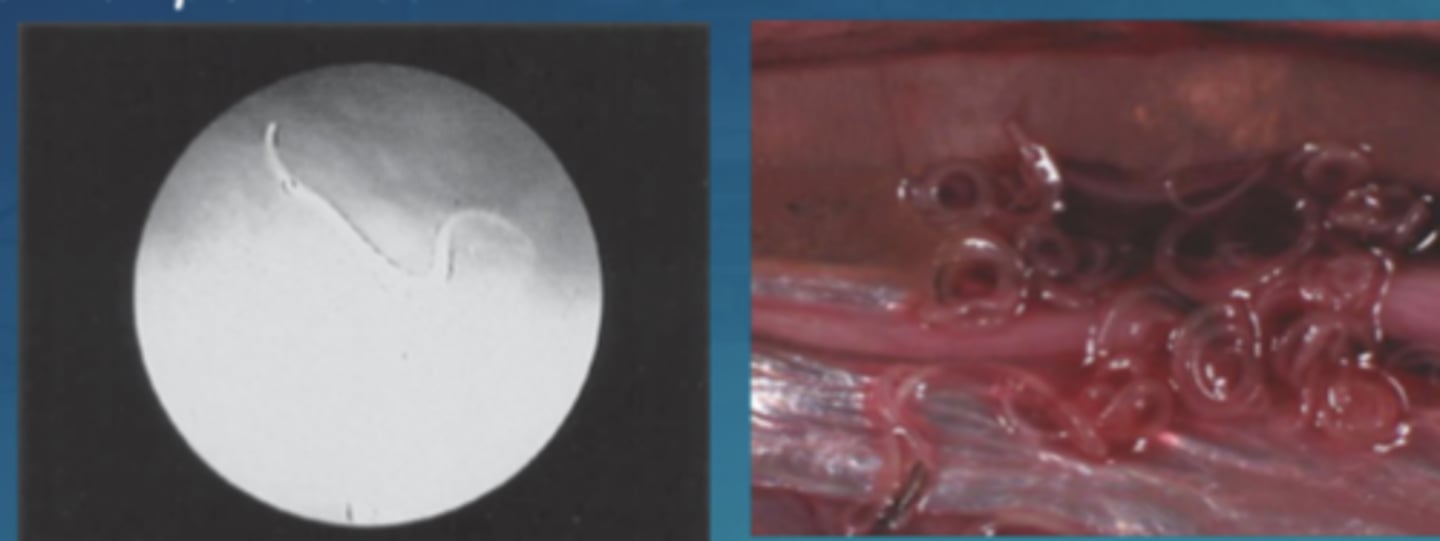

Anisakis larvae location in the fish

- free in the peritoneal cavity

- forming very numerous tangles attached to the peritoneum

- larvae coiled in a flat spiral and encapsulated in peritoneum, mesentery, liver or muscles often hypoxial